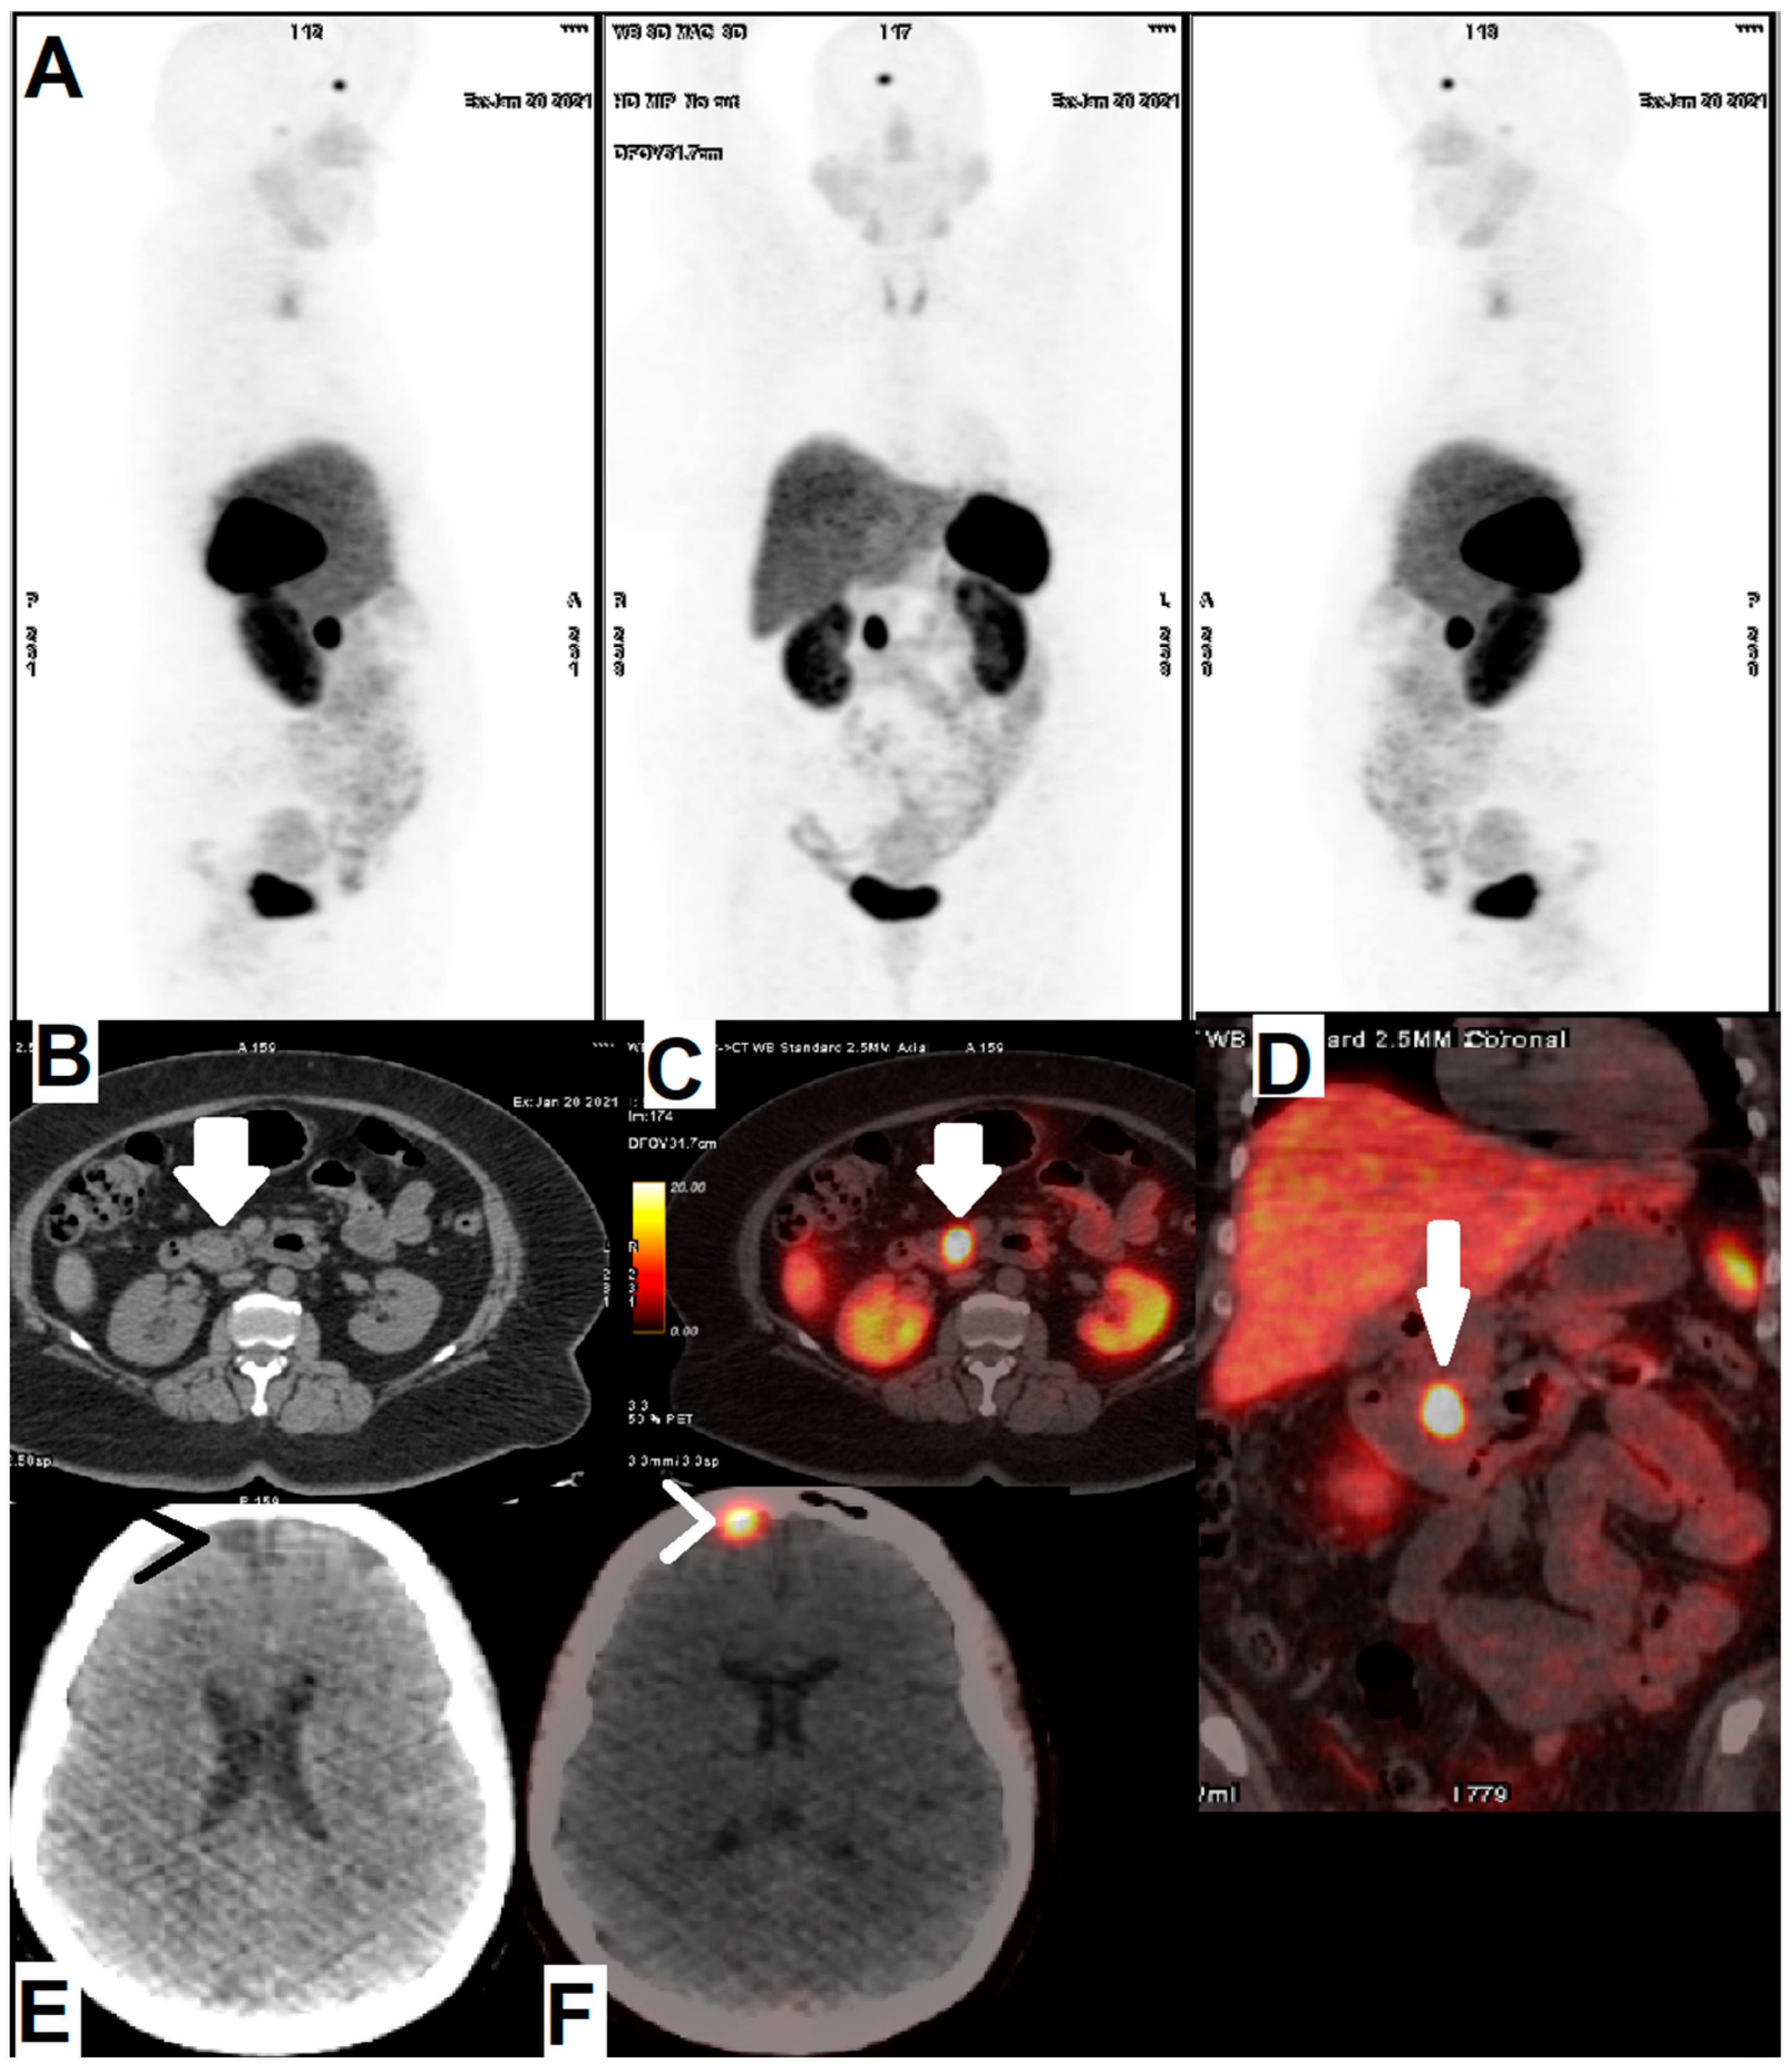

- Pfeifer, A.; Knigge, U.; Mortensen, J.; Oturai, P.; Berthelsen, A.K.; Loft, A.; Binderup, T.; Rasmussen, P.; Elema, D.; Klausen, T.L. Clinical PET of neuroendocrine tumors using 64Cu-DOTATATE: First-in-humans study. J. Nucl. Med. 2012, 53, 1207–1215. [Google Scholar] [CrossRef] [Green Version]

- Delpassand, E.S.; Ranganathan, D.; Wagh, N.; Shafie, A.; Gaber, A.; Abbasi, A.; Kjaer, A.; Tworowska, I.; Núñez, R. 64Cu-DOTATATE PET/CT for imaging patients with known or suspected somatostatin receptor–positive neuroendocrine tumors: Results of the first US prospective, reader-masked clinical trial. J. Nucl. Med. 2020, 61, 890–896. [Google Scholar] [CrossRef]

- Loft, M.; Carlsen, E.A.; Johnbeck, C.B.; Johannesen, H.H.; Binderup, T.; Pfeifer, A.; Mortensen, J.; Oturai, P.; Loft, A.; Berthelsen, A.K. 64Cu-DOTATATE PET in patients with neuroendocrine neoplasms: Prospective, head-to-head comparison of imaging at 1 hour and 3 hours after injection. J. Nucl. Med. 2021, 62, 73–80. [Google Scholar] [CrossRef] [PubMed]

| [64Cu]Cu-DOTA-Octreotide Derivatives | Disease | Patients Included in the Study | Year | Result | Refs. |

|---|---|---|---|---|---|

| [64Cu]Cu-DOTA-TATE | NET | 12 patients divided into 3 dose groups | 2020 | This protocol was introduced as a safe imaging method provides high quality and accurate images using optimal dose of 148 MBq (4.0 mCi) injection | [92] |

| NET | 60 | 2015 | Potential role of 64Cu-DOTATATE in the assessment of atherosclerosis was confirmed | [23] | |

| NEN | 128 | 2020 | The study demonstrated prediction potency of [64Cu]Cu-DOTA-TATE in PFS | [24] | |

| NET | 112 | 2015 | Superiority of [64Cu]Cu-DOTA-TATE over [111In]In-DTPA-OC was proved | [5] | |

| NEN | 35 | 2020 | Excellent performance of [64Cu]Cu-DOTA-TATE PET/CT during 1–3 h after injection was clarified | [95] | |

| [64Cu]Cu-DOTA-TOC | NET | 33 | 2019 | High detection rate and high target to background ratio in images raised [64Cu]Cu- DOTA-TATE as a promising and safe radiolabeled SST derivative for NET detection | [22] |